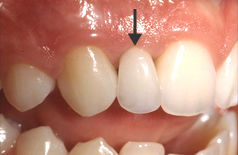

インプラントを埋入する部位の歯肉を開き、顎の骨にインプラントを埋入します。インプラントが骨にしっかり結合するまで約3ヶ月程度待ちます。 この間、必要に応じて仮歯を入れることもできますので、日常生活に差し支えありません。